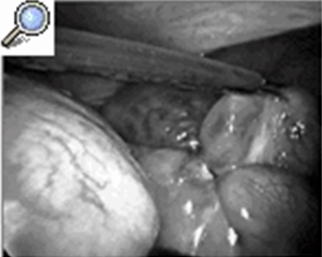

En esta tabla Nº 7 valoramos la presencia de compromiso vascular o no del asa intestinal, observando que en 97 pacientes no se presentó compromiso vascular para un 89,0%.

En 12 pacientes se presento gangrena del asa comprometida para un 11,0%, estos pacientes llevaban todos más de 48 horas desde el inicio de su sintomatología y la llegada a nuestros centros, en la mayoría de los pacientes eran de edad avanzada donde ya por el envejecimiento normal del organismo existe un déficit de irrigación de los tejidos, además llegaron ya con serias alteraciones de su medio interno repercutiendo en sus funciones respiratorias y cardiovasculares, esto demuestra que el tiempo de evolución desde el comienzo de su cuadro oclusivo hasta que se lleva a cabo su tratamiento quirúrgico definitivo es directamente proporcional a la gravedad y al pronóstico del paciente.

El 89,0% de los pacientes no tuvo compromiso vascular a pesar de tener todos más de 48 horas de evolución cuando llegaron a nosotros y la mayoría haber sido atendidos en otras instituciones hospitalarias. Todos nuestros pacientes recibieron una preparación pero-operatoria de menos de 12 horas y en los casos que se sospecho la estrangulación el periodo preoperatorio no excedió de 4 horas.